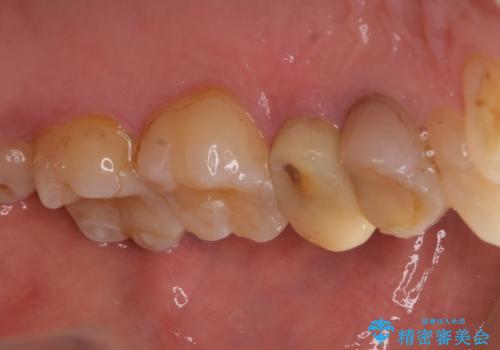

- 2年ほど放置していた左上の仮歯がとれたことをきっかけにご来院された患者様です。

セラミック治療がご希望でしたが、ときどき歯肉が腫れるということで根管治療もご希望されました。

左上の仮歯を2年使用して穴があいて外れたことをきっかけにご来院されました。

レントゲン上からも、歯の中(根管)が汚れている可能性があることをご説明したところ、根管治療からやり直しをすることになりました。